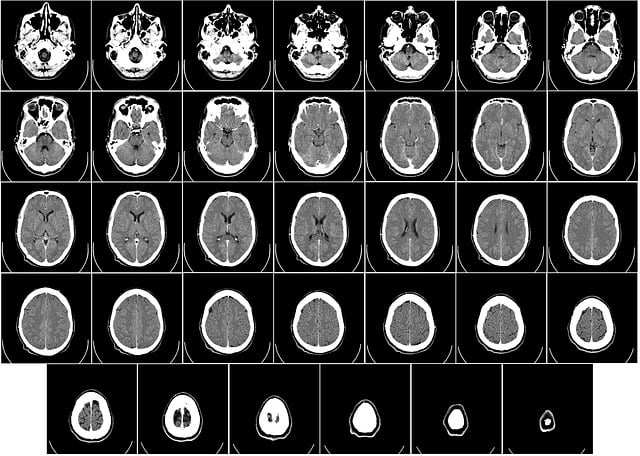

- 뇌 MRI(무증상 일반 스크리닝)

- 이유: 방사선은 없지만 비용 대비 건진 효율 낮음. 두통·신경학적 증상·이상 소견(뇌종양, 뇌경색, 치매 등) 있을 때 시행.